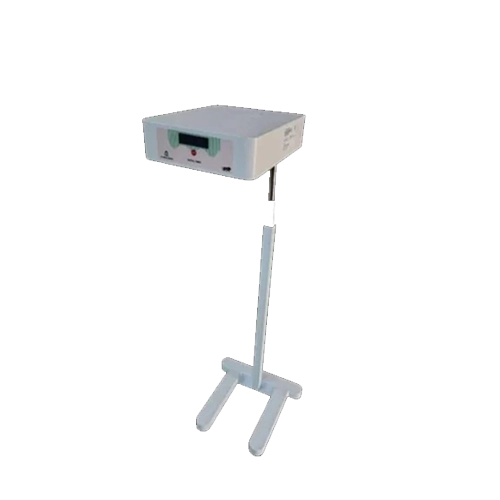

Alxa Medical Technology LLP is a specialized Bubble CPAP Machine Manufacturers in Noida, focused on delivering end-to-end neonatal and critical care medical equipment for modern healthcare facilities. Our comprehensive product range includes Nasal Prongs and Nasal Masks for safe oxygen delivery, advanced Ventilators for controlled respiratory support, and precision-based Syringe Pumps and Infusion Pumps for accurate medication and fluid administration. Each device is designed to meet the critical demands of NICUs and ICUs, ensuring reliability, ease of use, and consistent performance. By combining innovative engineering with medical-grade materials, we manufacture equipment that supports effective clinical decision-making and improved patient care.

As established Ventilator Suppliers in Uttar Pradesh, Alxa Medical Technology LLP provides healthcare institutions with a complete ecosystem of respiratory and infusion solutions. From initial oxygen therapy using Nasal Prongs and Nasal Masks, to advanced mechanical ventilation with Ventilators, and controlled infusion through Syringe Pumps and Infusion Pumps, our products are designed to function together seamlessly. We prioritize timely supply, quality assurance, and dependable service support, enabling hospitals to maintain uninterrupted critical care operations. Our solutions are trusted for their compatibility, durability, and adaptability in high-pressure clinical environments.

Best Multipara Monitor in India

Alxa Medical Technology LLP is recognized for offering some of the Best Multipara Monitor in India. Our unified approach allows healthcare providers to manage respiratory support and infusion therapy with greater accuracy, safety, and efficiency. By delivering reliable equipment supported by professional service, we help hospitals enhance treatment outcomes and patient safety. With a strong commitment to innovation, quality excellence, and long-term partnerships, Alxa continues to strengthen its position as a trusted name in neonatal and critical-care technology nationwide.